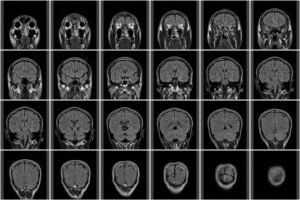

「めまい」や「耳鳴り」の症状がある時は、レントゲンやMRIで異常がある場合と、検査上は異常がない場合があります。

「めまい」や「耳鳴り」の症状でレントゲン・MRIで異常がある場合

MRIで器質的な変化が確認された場合、以下のような病態が「めまい・耳鳴り」を引き起こしている可能性があります。